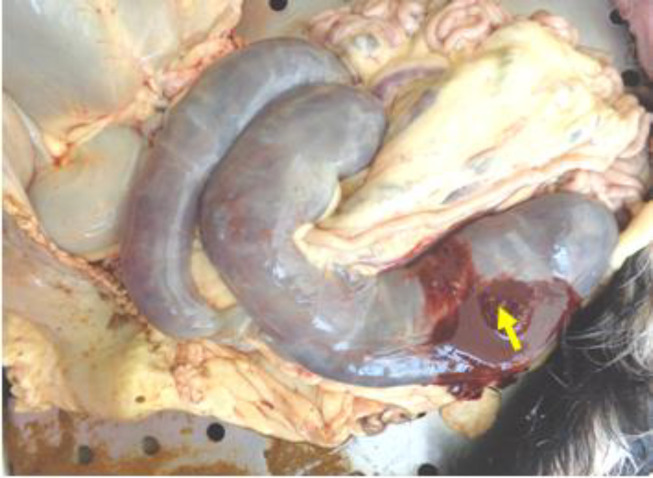

Findings/treatment and outcome: Postmortem examination showed mesenteric lymphadenomegaly with greyish yellow viscous contents. Ileum contained scattered dark brownish tubular concretions inside the lumen. Colon and caecum had scattered firm serosal and mucosal nodules with caseous exudate. Lumen contained viscous haemorrhagic content. Mucosa of the colon showed numerous tiny ulcers. Urinary bladder serosa showed a focal firm nodule with caseous exudate and irregular firm mass. Microscopically, lung revealed oval inclusions with clear halo in pulmonary macrophages. Caecum and colon showed ulcers with necrotic core. Necrotic border showed multinucleated giant cells and oval bodies with clear halo. Mesenteric lymph node and urinary bladder revealed pyogranulomatous inflammation with aggregation of macrophages filled with numerous tiny inclusions. Periodic acid-Schiff and Grocott's methanamine silver staining techniques and morphological features of the inclusion confirmed it as Histoplasma capsulatum. The case showed a resemblance with human colonic histoplasmosis.